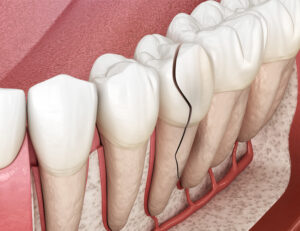

【リスク1】「骨吸収」の進行:土台が急速に溶けていく

歯の根の割れ目に潜み、増殖した細菌は、根の周りを囲んでいる「歯槽骨(しそうこつ)」という骨を攻撃し始めます。

体は炎症から自分を守るための防御反応として、感染源である歯の根から遠ざかろうと、自ら骨を溶かしてスペースを作ります。

これが「骨吸収」です。

最初は自覚症状が少ないこともありますが、レントゲンを撮ると歯の根の周りに「透過像」と呼ばれる黒い影(骨がなくなっている部分)がはっきりと確認できるようになります。

骨は一度大きく失われると、自然に元の形へ戻ることは困難です。

歯を支える土台が崩れることで、後に解説する治療の選択肢が狭まる最大の原因となります。